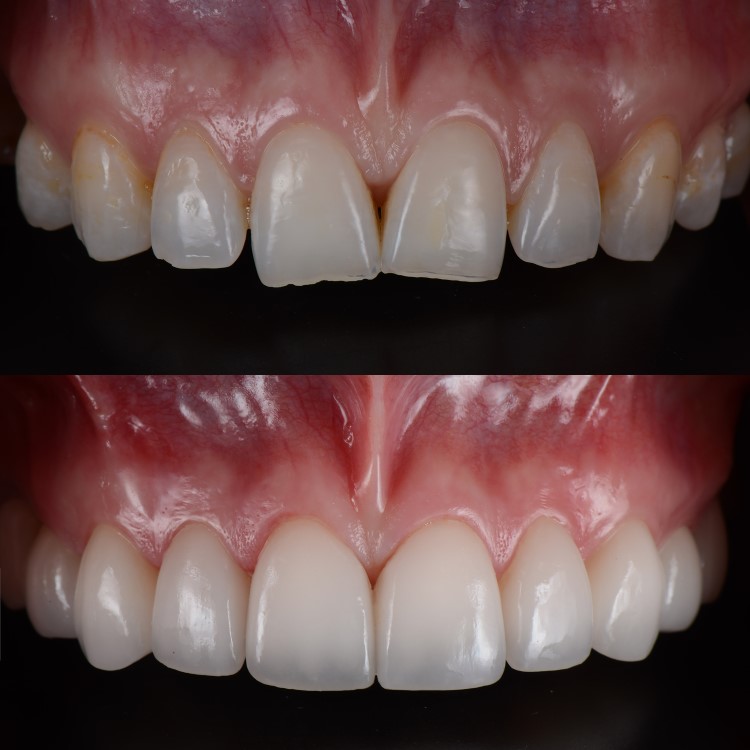

COMPOSITE VENEERS

MILD GAP CLOSURE

TEETH BLEACHING

BLACK OR BROWN COLOURED TOOTH CORRECTION TREATMENT